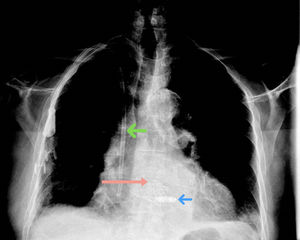

Paciente de 84 años con antecedentes de trombosis venosa profunda anticoagulado con acenocumarol, hipertensión arterial y enfermedad renal grado IV en hemodiálisis mediante catéter permanente subclavio derecho (fig. 1, flecha verde).

Ingresado en el hospital para implante de prótesis aórtica percutánea (fig. 1, flecha rosa) por estenosis aórtica muy severa y alto riesgo quirúrgico. Al tercer día del procedimiento, presentó bloqueo auriculoventricular completo con ritmo de escape con morfología de bloqueo de rama derecha similar al basal a 29lpm (fig. 2A).

Presentaba un alto riesgo de complicaciones vasculares con un sistema de estimulación convencional (infección del sistema de la prótesis aórtica y del catéter permanente), así como un elevado riesgo hemorrágico. Por ello se decidió implante de marcapasos sin cables AV para favorecer la sincronía auriculoventricular (fig. 1, flecha azul). El procedimiento se realizó sin complicaciones, con una detección de onda R de 8,5mV y un umbral de 0,5V a 0,24ms con una correcta sincronía AV (fig. 2B).